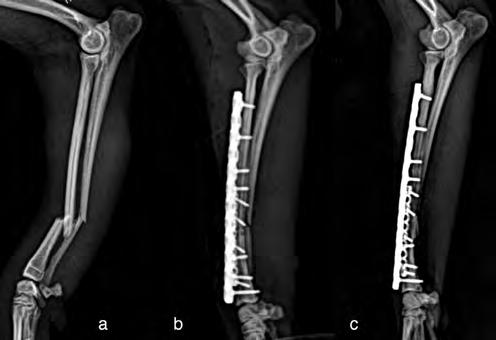

Después de la cirugía se analizaron las radiografías postoperatorias, realizándose las mismas mediciones que en la planificación, y observándose cómo los valores obtenidos tras la cirugía se correspondían con los valores planificados (Fig. 5). Se colocó un vendaje postoperatorio sencillo durante 14 días, para evitar la manipulación del área quirúrgica por parte de la pa-

Figura 5. Proyecciones radiográficas craneocaudal y mediolateral posquirúrgicas. Las radiografías muestran el resultado tras la cirugía.

Figura 7. Proyecciones radiográficas (A) craneocaudal y (B) mediolateral a los 4 meses de la cirugía. Las imágenes muestran la avanzada consolidación de la ostectomía.